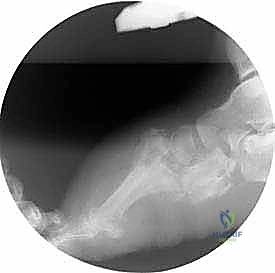

عندما تتضافر هاتان النظريتان، ينهار قوس القدم تماماً، وتبرز العظام نحو الأسفل، مما يخلق ما يُعرف بـ "قدم الكرسي الهزاز" أو "قدم الروكر" (Rocker-bottom Foot)، حيث يصبح باطن القدم محدباً بدلاً من أن يكون مقعراً. هذا البروز العظمي يضغط بشدة على الجلد من الداخل، مما يؤدي سريعاً إلى تقرحات عميقة، التهابات بكتيرية، وتسمم الدم، وهو ما ينتهي غالباً بالبتر إذا لم يتم التدخل الجراحي المتخصص في الوقت المناسب.

- المرحلة الثالثة (مرحلة التصلب وإعادة البناء): تبرد القدم وتستقر، لكنها تلتئم على وضع مشوه بشدة (قدم الروكر)، مما يمهد الطريق للتقرحات المستعصية.